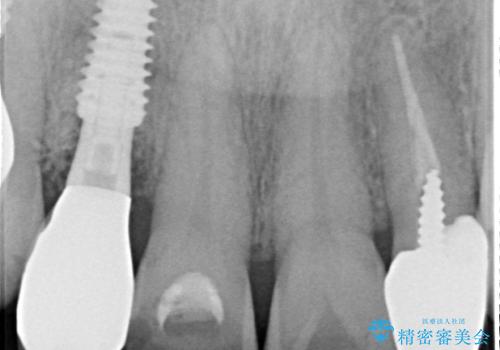

臼歯はもはや咬み合わせに寄与していない状態であり、3歯を抜去してインプラント2本埋入によるブリッジ補綴を計画しました。

臼歯部は前歯以上に炎症が酷く、抜歯即時埋入不可と判断されましたが、従来法よりは短期間で終えることができました。